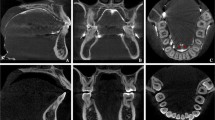

Landmarks were established for the tongue space (Fig. 1 and Table 1). The superior border of the tongue space was the palatal plane [anterior nasal spine (ANS) to posterior nasal spine (PNS)], parallel to the Frankfort horizontal plane (Fig. 2). This included the height of the palatal vault (HPV), which was the distance from the maxillary occlusal plane (tangential to the most distal points of the maxillary first molars) to the deepest point of the palate in the plane. The anterior border of the tongue space was the cingulum of the anterior teeth when they are in maximum intercuspation. The lateral border of the tongue space was the lingual side of the mandible (both right and left) all the way forward to the genial tubercle (GT). The inferior border of the tongue space was the hyoid bone to the genial tubercle and the anteroinferior point of the third cervical vertebra (C3) (Fig. 3). The posterior border of the tongue space was the left and right side gonion (Go) perpendicular to the Frankfort horizontal plane.

Landmarks for measuring tongue space. The superior landmarks and border of tongue space is the palatal plane [anterior nasal spine (ANS) to posterior nasal spine (PNS)], parallel to the Frankfort horizontal plane [orbitale (Or) to porion (Po)]. The lateral landmark is the lingual of the mandible from gonion (right and left) to the genial tubercle (GT); the lingual side of the dentition is also part of the lateral border. Posteriorly, the tongue space goes all the way to the gonion of the mandible and includes part of the airway, specifically portions of the oropharynx and hypopharynx. The inferior border of the tongue space is the hyoid bone to the GT and to the most anteroinferior point of the third cervical vertebra (C3)

Posteriorly, the tongue space includes part of the airway, specifically part of the oropharynx. The oropharynx was divided into two areas: velopharynx and glossopharynx [22]. The velopharynx was defined from the horizontal level of the palatal plane to the horizontal level of the end of the uvula. The glossopharynx was defined from the horizontal level of the end of the uvula to the horizontal level of the C3 (the most anteroinferior point of the third cervical vertebra) [23]. The overall tongue space included the oral cavity and part of the airway superior to the hyoid bone to GT and anteroinferior point of C3 and inferior to the palatal plane (Fig. 1).

In this study, the landmarks circumscribing the areas of interest were carefully selected based on the anatomy of the tongue and airway (Fig. 1 and Table 1). Each of these landmarks is easily recognizable and by having a standardized protocol for capturing CBCT images, these landmarks should provide accurate and reproducible measurements. The overall tongue space has to reflect all the space that the tongue occupies during normal activities such as breathing, speech, swallowing, and mastication. Several of the chosen landmarks were hard tissue instead of soft tissue because the soft tissues are continuously moving or may move depending on the activities.

The superior border of the tongue space was the palatal plane [anterior nasal spine (ANS) to posterior nasal spine (PNS)]. This was chosen because there were lots of changes to the position of the soft palate. For example, on the onset of the swallowing reflex, the soft palate is being drawn upward [36]. Posteriorly, the tongue space reaches the gonion of the mandible, and part of the airway, specifically portions of the oropharynx, which can be divided into the velopharynx and glossopharynx. The oropharynx extends from the soft palate to the most anteroinferior part of the C3 and includes the base of the tongue [37]. The inferior landmarks include the genial tubercle, hyoid bone, and anterior, inferior of C3. The reason we chose the landmarks described above is that the floor of the mouth consists of the geniohyoid and mylohyoid muscle. The origin of the geniohyoid muscle is the inferior mental spine of the mandible, while the insertion is the hyoid bone. The origin of the mylohyoid muscle is the mylohyoid line of the mandible, and the insertion of the muscle is the body of the hyoid bone. The C3 was chosen, because the hyoid bone lies at the level of C3 [38]. Since the hyoid bone is the inferior border of the tongue space, we proposed the C3 is a good reference point for the posteroinferior portion of the tongue space.